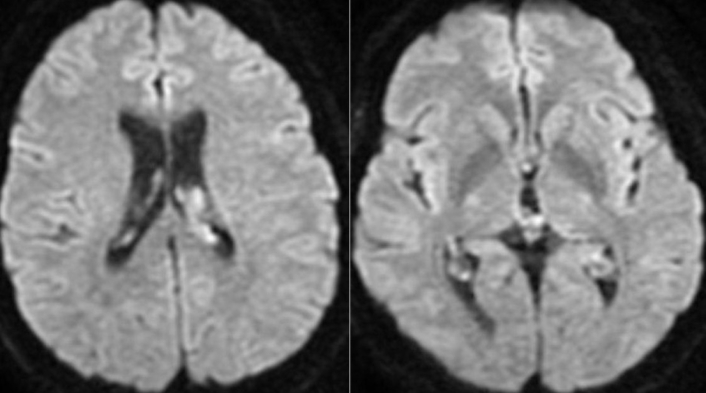

A 30-year-old male Lebanese patient was received at the emergency department initially manifesting mild headache and emesis over the weekend in the inaugural week of March 2023. Preliminary laboratory analyses yielded normative outcomes. A cranial computed tomography (CT) exhibited regular findings except for marginal engorgement of the choroid plexus within the lateral ventricles (Figure 1). Despite the absence of neurologic deficits, subsequent magnetic resonance imaging (MRI) disclosed a comparable indefinite irregularity of the choroid plexus (Figures 2 and 3). CSF examination demonstrated standard parameters for glucose, protein, white blood cells, and red blood cells. Additional inquiries, encompassing echocardiography and carotid imaging, yielded unremarkable results. The patient lacked notable medical history but exhibited elevated cholesterol levels and was on a regimen of aspirin 81 mg, clopidogrel 75 mg, and atorvastatin 40 mg. Following discharge with analgesic therapy, the family reported alleviation of the headache. However, a few days later, the patient revisited the emergency department with exacerbated cognitive impairment, confusion, and lethargy. A second urgent MRI unveiled heightened choroid plexus congestion and hypodense lesions in the pons (Figures 4 and 5). Lumbar puncture (LP) indicated elevated white blood cells, elevated glucose, and diminished protein levels, culminating in a vasculitis diagnosis. Steroid therapy, namely methylprednisolone 500 mg every 12 h, was initiated. Concomitantly, further deterioration of the neurological status of the patient ensued despite steroid therapy, leading to choroid plexus edema and hydrocephalus, necessitating ventriculoperitoneal shunt (VPS) placement. The patient’s condition deteriorated further, with a Glasgow Coma Scale score of 10, Karnofsky’s performance status at 10–20%, and Zubrod stage 4. An urgently conducted choroid plexus biopsy during the same procedure revealed evidence of diffuse large B-cell lymphoma (DLBCL). Postoperative complications in the intensive care unit necessitated a second VPS due to hydrocephalus and obstruction of the initial catheter by proliferating choroid plexus tissue (Figure 6). Despite diminished reflexes and increased oxygen requirements, the patient remained responsive to pain. DLBCL treatment involved intravenous methotrexate, intrathecal cytarabine, and rituximab, followed by 18 radiotherapy sessions. Post-chemotherapy, the patient exhibited confusion, short-term memory deficits, and orientation primarily toward immediate family members. However, a gradual improvement in neurological status was noted during the radiotherapy course. As of August 2023, the patient has completed the requisite radiotherapy sessions. During the last assessment in December 2024, the individual was conscious, cooperative, and oriented. Lingering minor lower limb weakness is progressively improving through physiotherapy. On the Karnofsky scale, the patient registers at 60%, corresponding to Zubrod stage 2.

Diffuse-weighted magnetic resonance imaging (MRI) in the axial view showing a high signal in the choroid plexus of the lateral ventricles